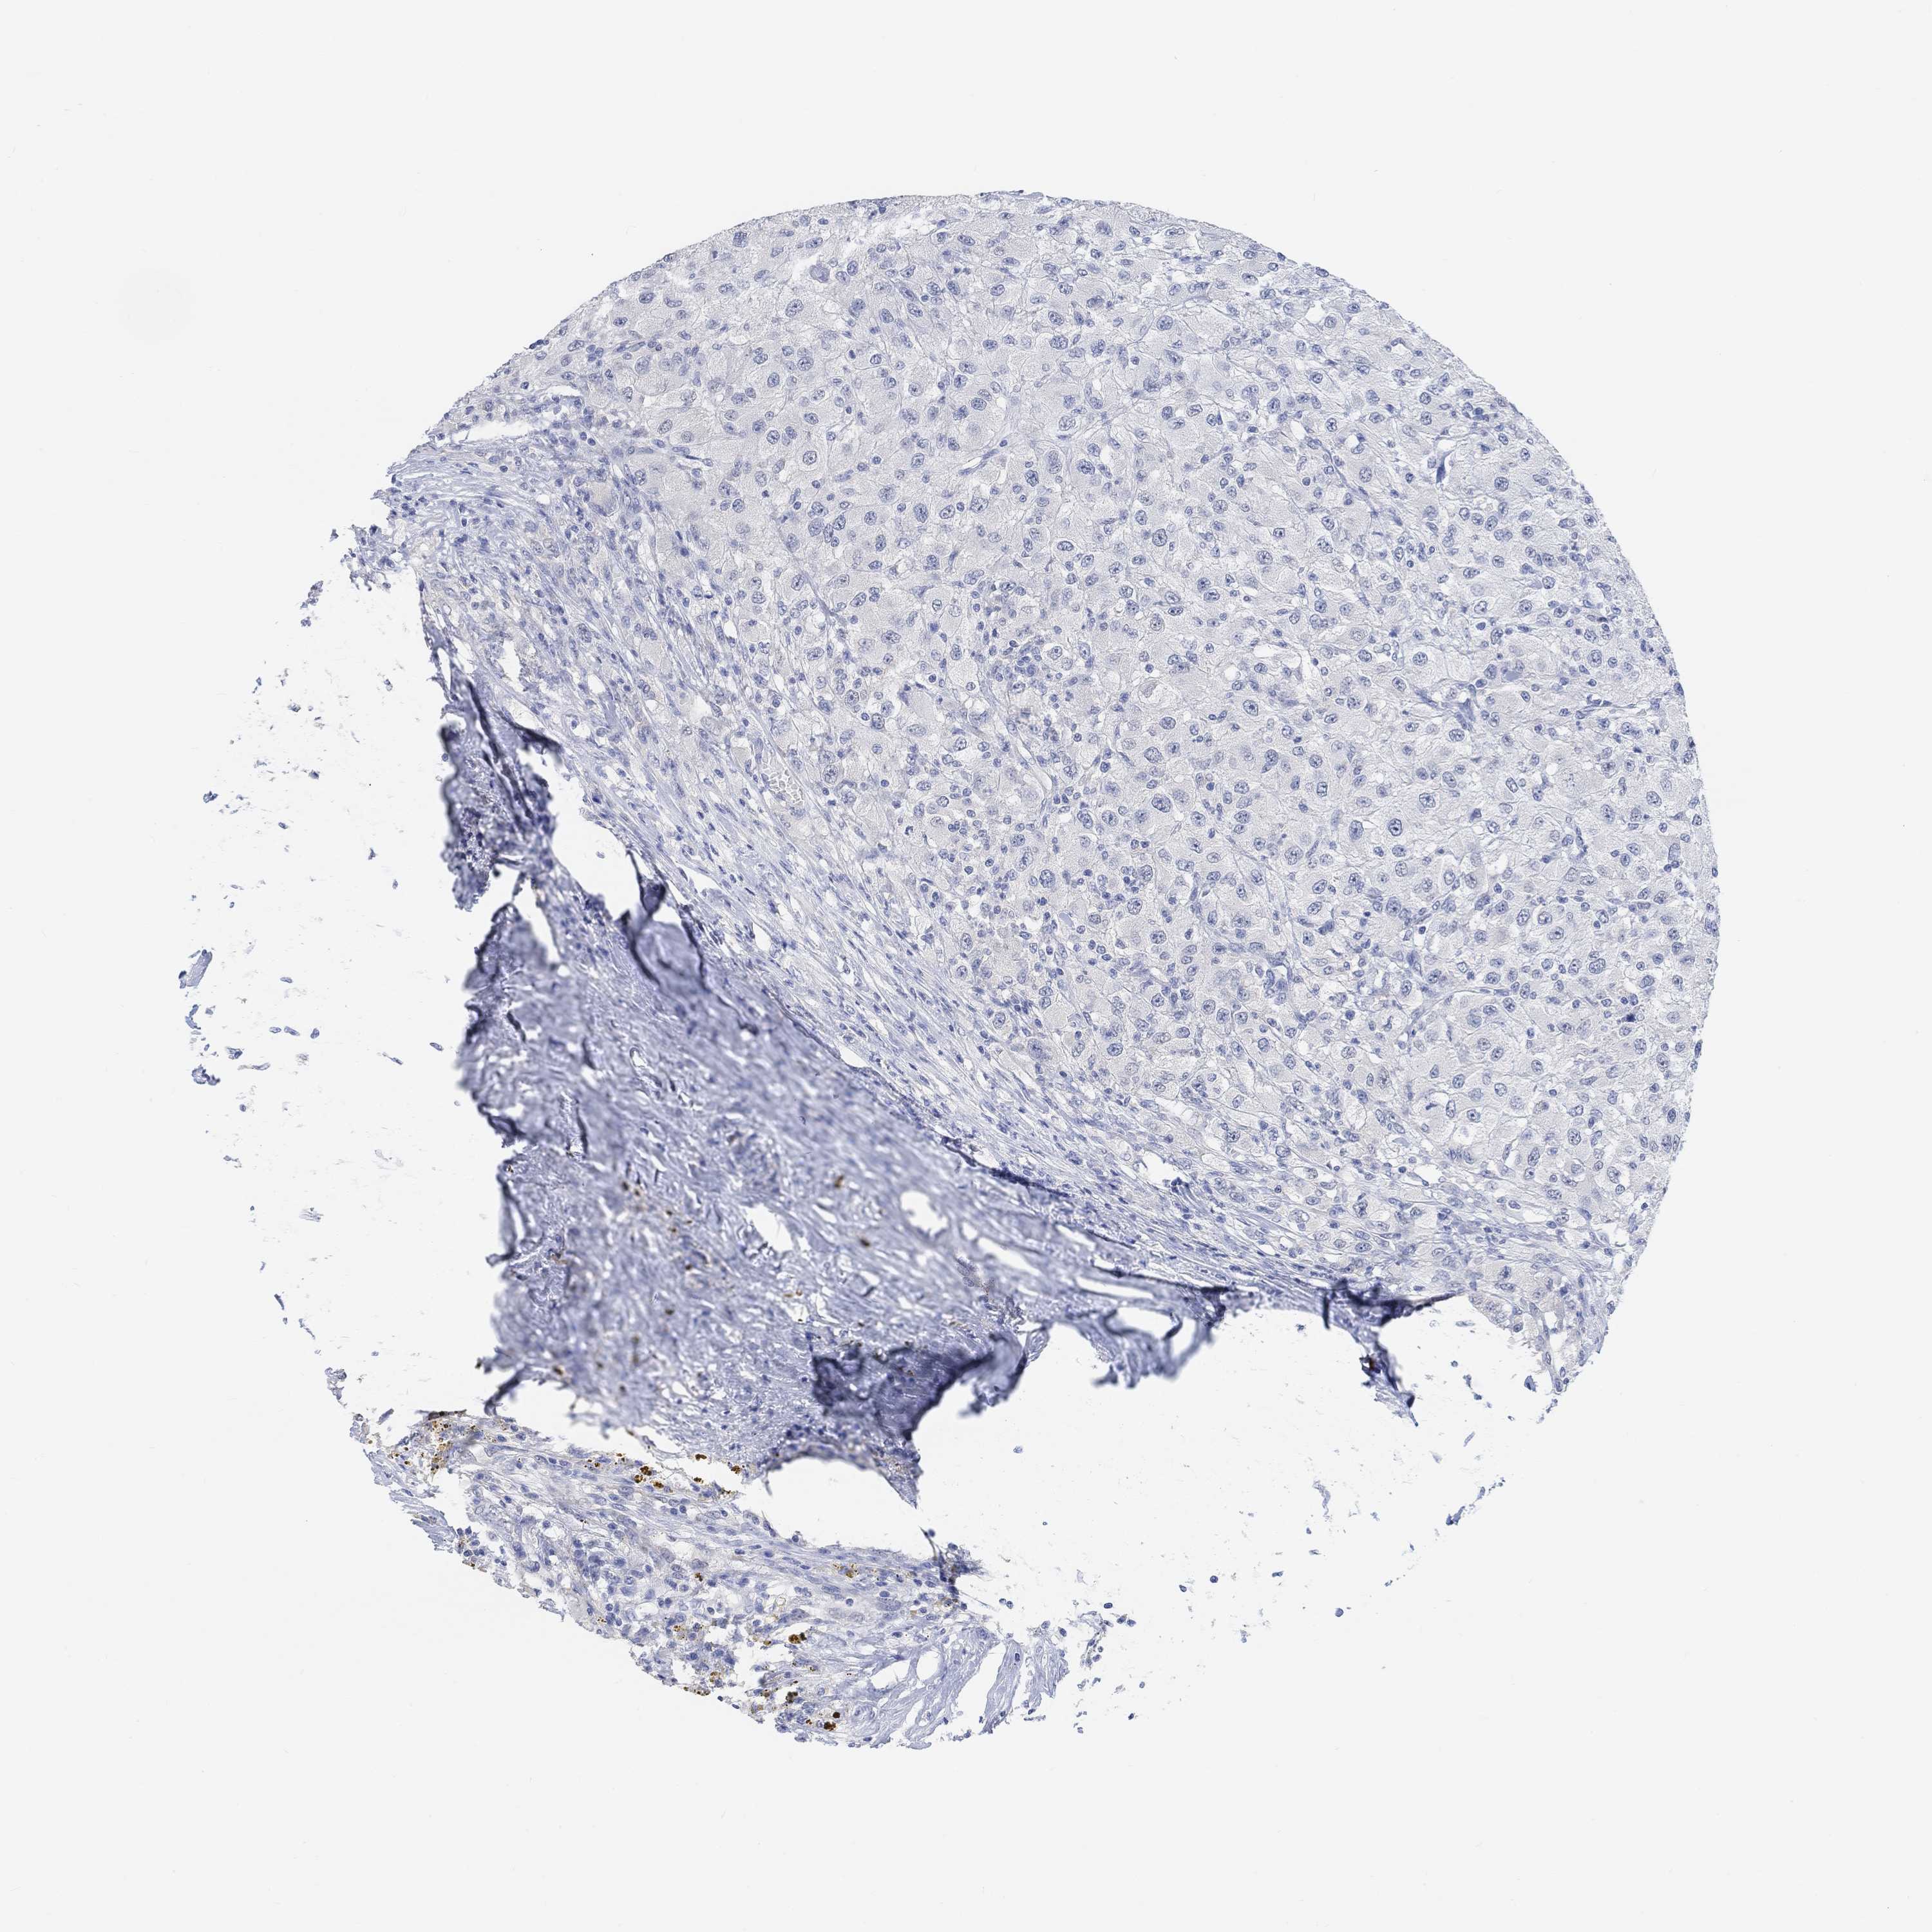

KIDNEY RENAL CLEAR CELL CARCINOMA (VALIDATION) - Interactive survival scatter ploti

MUC1 is not prognostic in Kidney Renal Clear Cell Carcinoma (validation)

: 24.39

Average pTPM 95.3

Number of samples 100